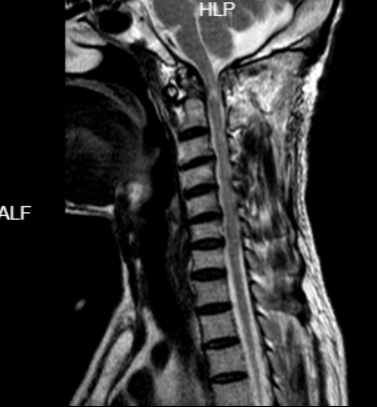

59岁的患者黄先生1年前开始出现四肢麻木、乏力,并逐渐出现行走困难及大小便障碍,因其为低保户,经济困难,一直未正规治疗,后症状逐渐加重,入院前已经出现四肢无力以及大小便困难,收入我院骨科一区治疗。入院检查MR提示“寰枢椎脱位、椎管狭窄、脊髓受压”。

术前与术后对比图